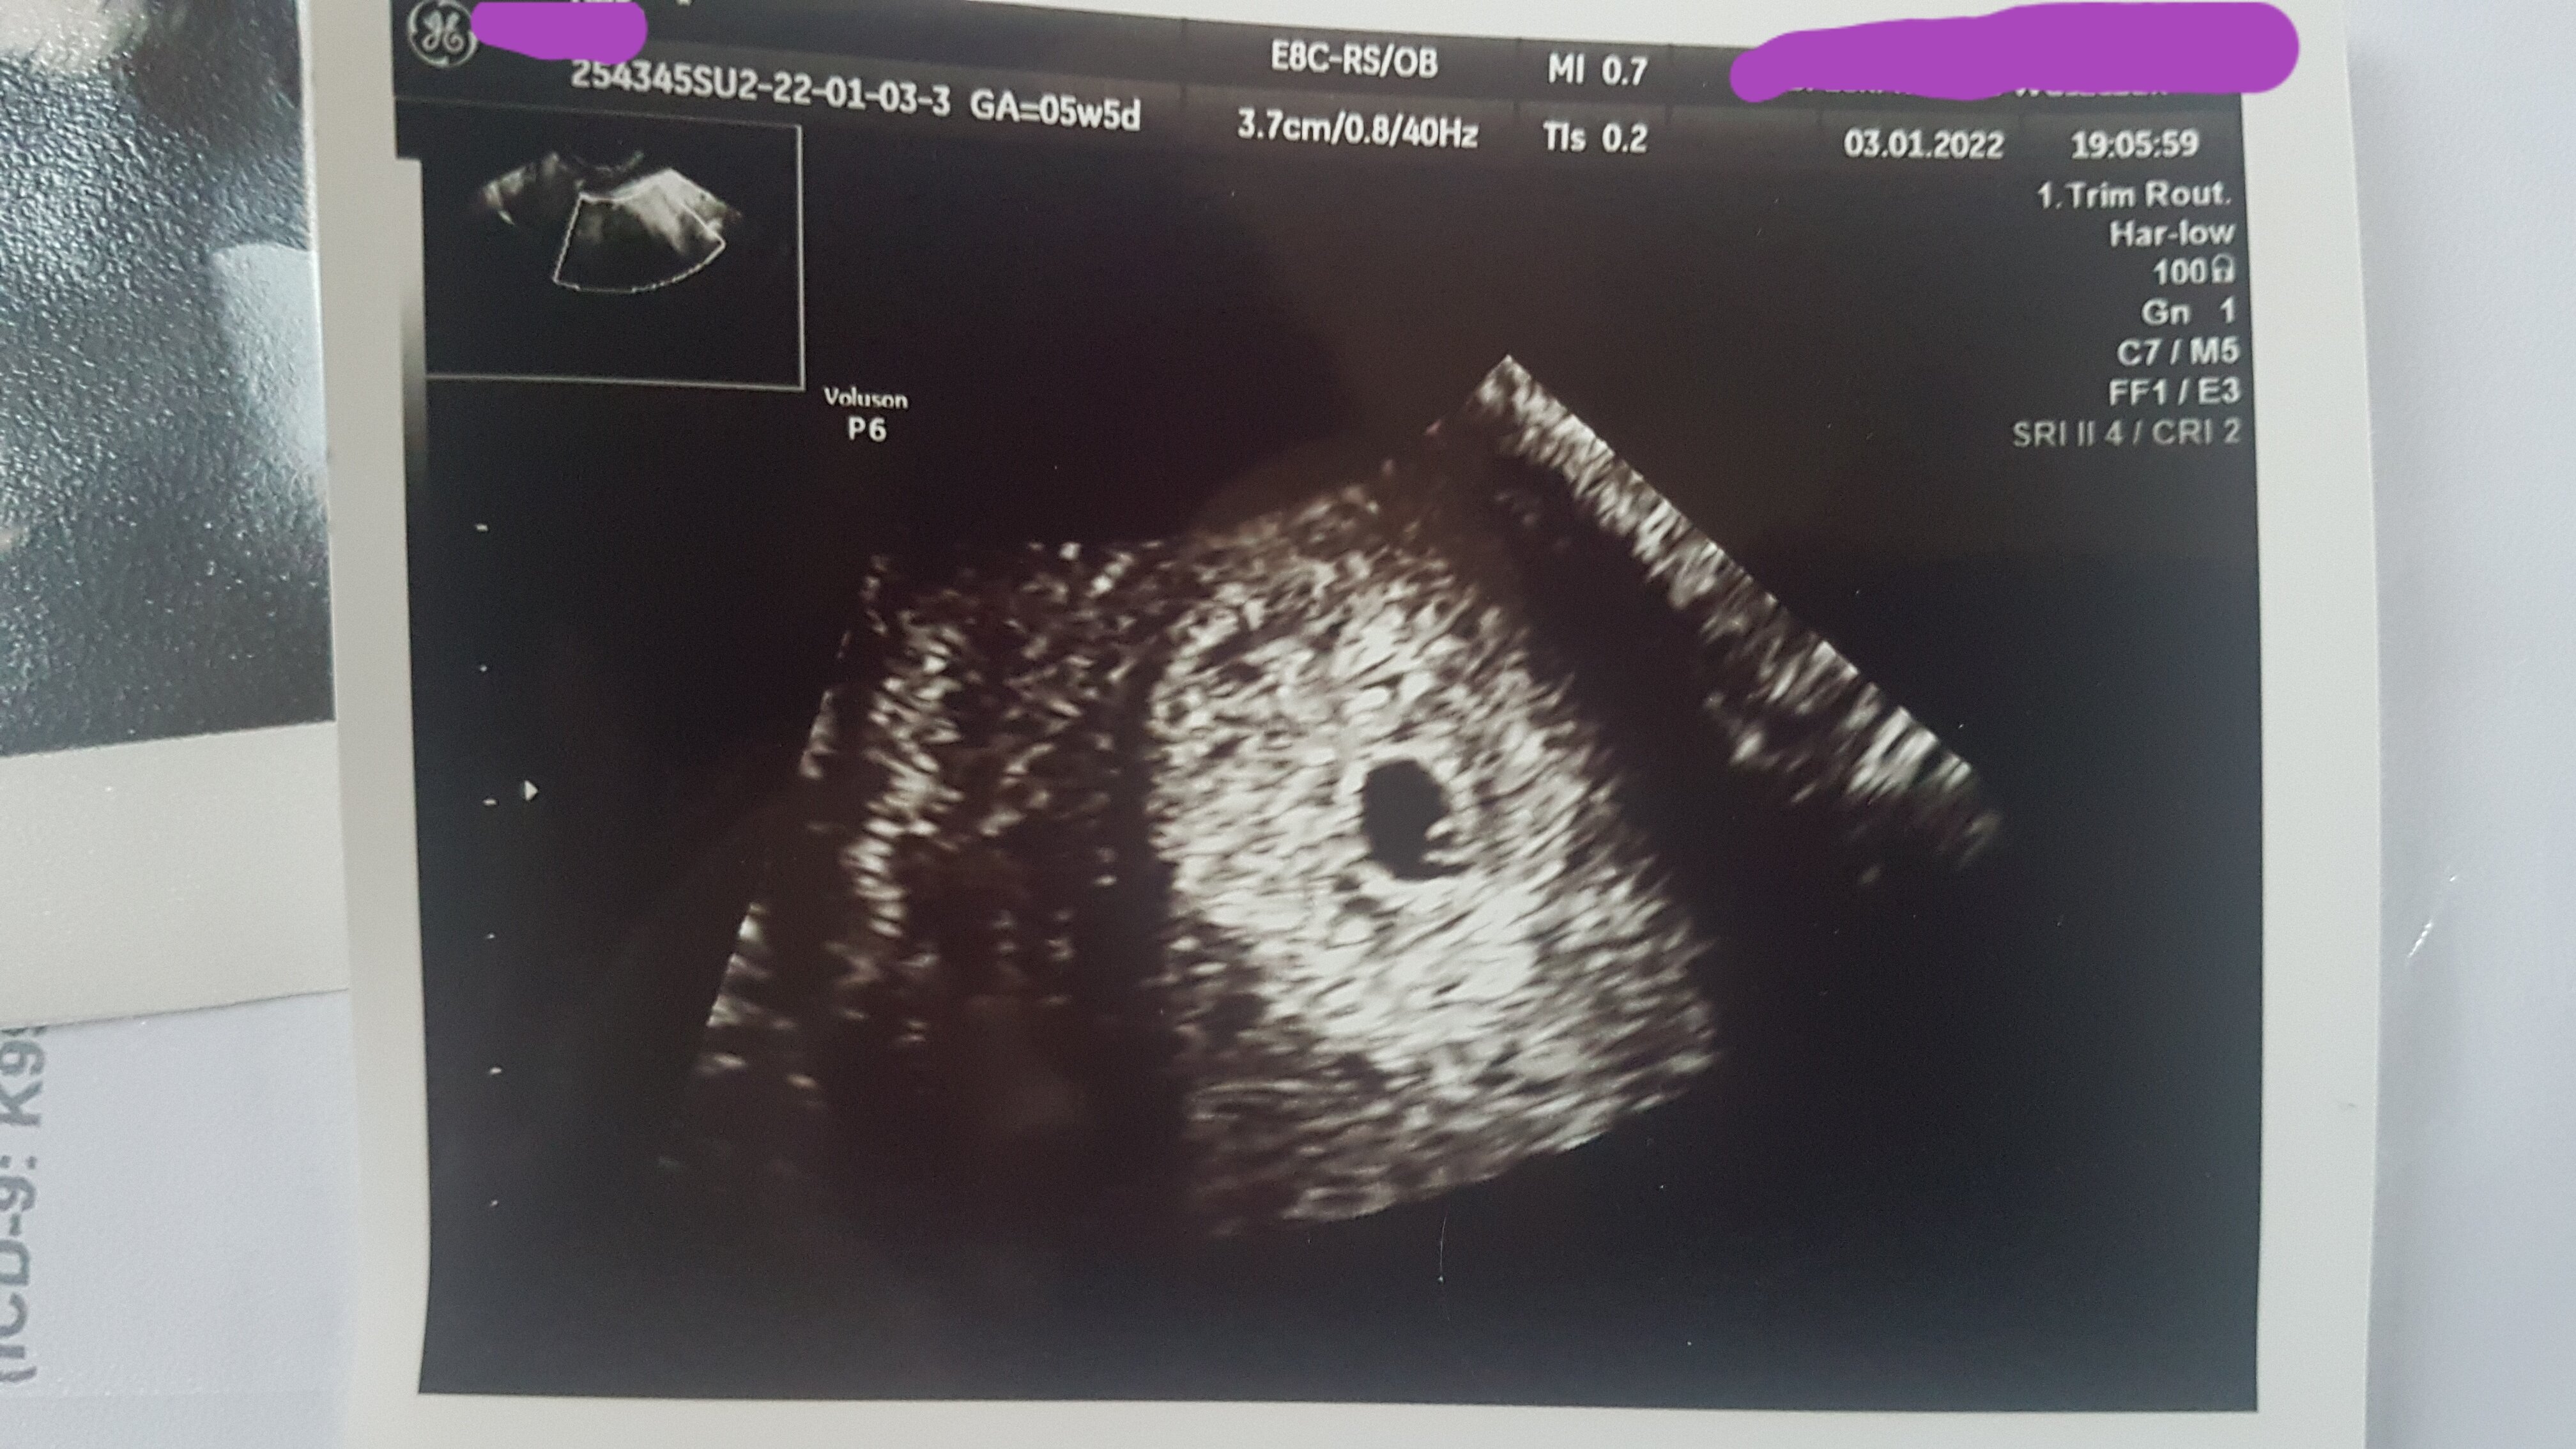

3.01.2022 roku powtórzyłam bhcg i wynik to 1380,4, więc wzrost 43%, a progesteron spadl do 11,9... szczerze to się załamałam😭 w ten sam.dzien pojechałam do ginekologa ( 5t 5d) po zrobieniu usg stwierdził pęchęrzyk ciążowy z ciałkiem żółtym w macicy, zabronił robić dalej bhcg i mam brać duphaston. Dodatkowo n prawym jajniku z którego była owulacja ginekolog stwierdził torbiel 2cm ale wedlug niego jest progwsteronowa i to dobry znak. Co Wy o tym myślicie?

Dziewczyny, załączam zdjęcie z usg. Z tego stresu nawet nie zapytalam ginekologa,czy wszelkie wymiary są w normie 😓

W 5+5 to normalne że nie ma zarodka. Poki co obraz z USG jest okej, a bety się nie bada jak ciąża jest uwidoczniona na USG, może ona już różnie rosnąć. Ja w 4+5 tygodniu miałam przyrost o bodajże 30 %, ale ciąża była widoczna na USG więc na betę już nie patrzyliśmy